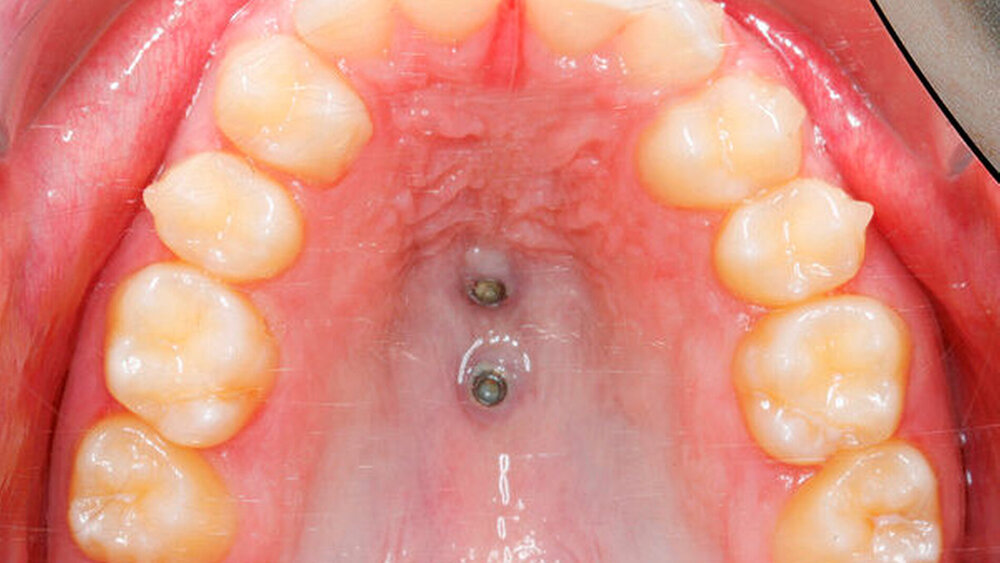

Das zweiphasige Vorgehen wird anhand eines 15-jährigen Patienten mit Aplasie beider oberer seitlicher Schneidezähne dargestellt (Abbildung 1). Die bleibenden oberen Eckzähne waren nach mesial gewandert, während die Milcheckzähne noch persistierten. Von Eltern und Patient wurde der kieferorthopädische Lückenschluss, möglichst mit Alignern, gewünscht. Die Behandlung begann mit dem Anpassen kieferorthopädischer Bänder auf den oberen ersten Molaren sowie der Insertion von zwei Mini-Implantaten (2 x 9 mm und 2 x 7 mm, Benefit, PSM) posterior der dritten Gaumenfalten in der sogenannten T-Zone [Becker, 2019; Wilmes, 2016]. Die Verbindung zu den Prämolaren wurde durch Gleitröhrchen (Tubes) und Klebeverbindungen mittels Composite realisiert (Abbildung 2, B-Mesialslider, [Wilmes, 2018]). Die Milcheckzähne wurden erst unmittelbar nach Einsetzen des Mesialsliders extrahiert, um die Geschwindigkeit des Lückenschusses zu erhöhen (Regional Accelatory Phenomenon – RAP [Verna, 2016]). Nach insgesamt zwölf Monaten sind alle Lücken nach mesial geschlossen (Abbildungen 3 und 4).